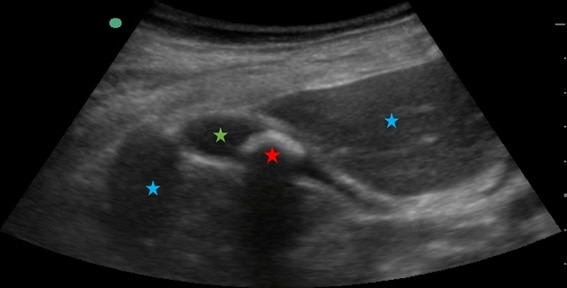

En la imagen siguiente, podemos distinguir el hígado (estrella azul, de una densidad determinada) de la vesícula (estrella verde, de un contenido líquido, de densidad menor) de la litiasis biliar (estrella roja, formada por calcio, de una densidad mucho mayor a las anteriores) porque entre cada una de estas estructuras se forma una interfase, al tener densidades (y por tanto impedancias) distintas.